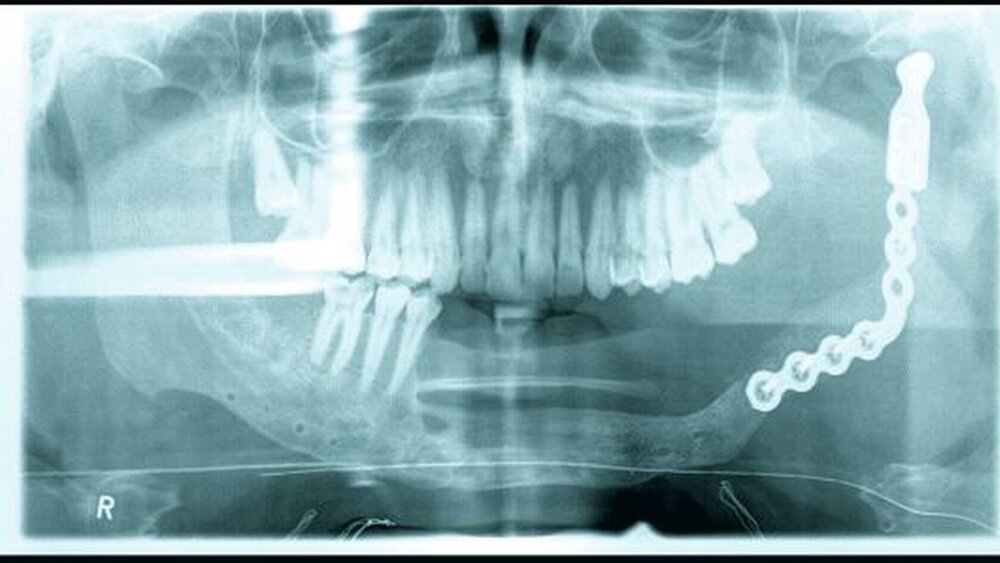

Die Diagnostik und die präoperative Vor- bereitung beinhalteten eine Computertomografie-Untersuchung (CT) des Gesichtsschädels und des Halses, eine Ganzkörperszintigrafie in Mehrphasentechnik und eine Single-Photon-Emmissions-Computertomografie (SPECT) sowie eine Probeexzision. Im CT (Abbildung 2) wurde eine monströse, vom Unterkiefer links ausgehende Raumforderung beschrieben, die zur völligen Destruktion der Knochenstruktur und zur Auftreibung des Unterkiefers geführt hatte. Die Tumorentität zeigte ein verdrängendes und kein infiltratives Wachstum. Somit waren keine eindeutigen Malignitätskriterien gegeben. Die nuklearmedizinische Untersuchung ergab den Befund einer mäßig vermehrten Perfusion und Vaskularisation im Bereich des monströsen Tumors der perimandibulären Region links. Auch hier zeigte sich eine nahezu vollständige Destruktion des Unterkiefers links bis einschließlich des linken Temporomandibulargelenks. Ein Anhalt für ossäre Metastasen ergab sich aus dieser Untersuchung nicht.

Nach Vorliegen der diagnostischen Befunde sowie der Konditionierung des Allgemeinzustands erfolgte die operative Versorgung des Patienten mittels Tumorresektion mit mittellinienüberschreitender Unterkieferresektion. Die entfernten Kieferanteile wurden zunächst durch eine Osteosyntheseplatte mit Gelenkendoprothese ersetzt. Das Tumor-resektat hatte eine Ausdehnung von 140 mm x 130 mm x 100 mm und ein Gewicht von 1376 Gramm (Abbildung 3).